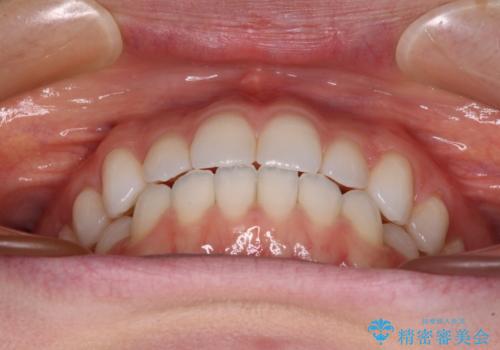

上下前歯が接触しない オープンバイトをインビザラインで改善

- 前歯の上下スペースによる食べにくさを気にして来院された患者様です。

インビザラインにより上下の前歯の隙間を閉じていくこととしました。

上下の奥歯を圧下させるようにすることで、前歯を接触させるように計画しました。

上下の隙間に舌が入り込むことがオープンバイトの原因であったため、舌の筋肉のトレーニングも並行して行い、後戻りの抑制を図りました。